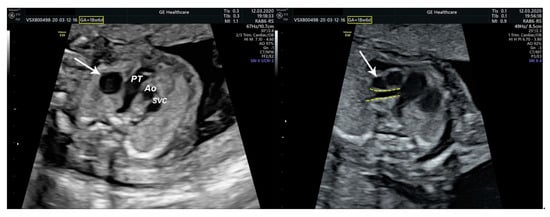

2.1. Ultrasound Findings

- an isolated aortic arch anomaly (supposedly aneurysmal dilation from which the left common carotid artery emerges) and coarctation of the aorta with the anterograde flow;

- ventricular septal defect, coarctation of the aorta, and a vascular formation located superior from the aortic arch with the appearance of an arteriovenous fistula;

- aneurysmal dilation located above the pulmonary trunk bifurcation and a dilated left common carotid artery with a retrograde flow;

- minor ventricular septal defect with a normal ductus venosus triphasic flow.